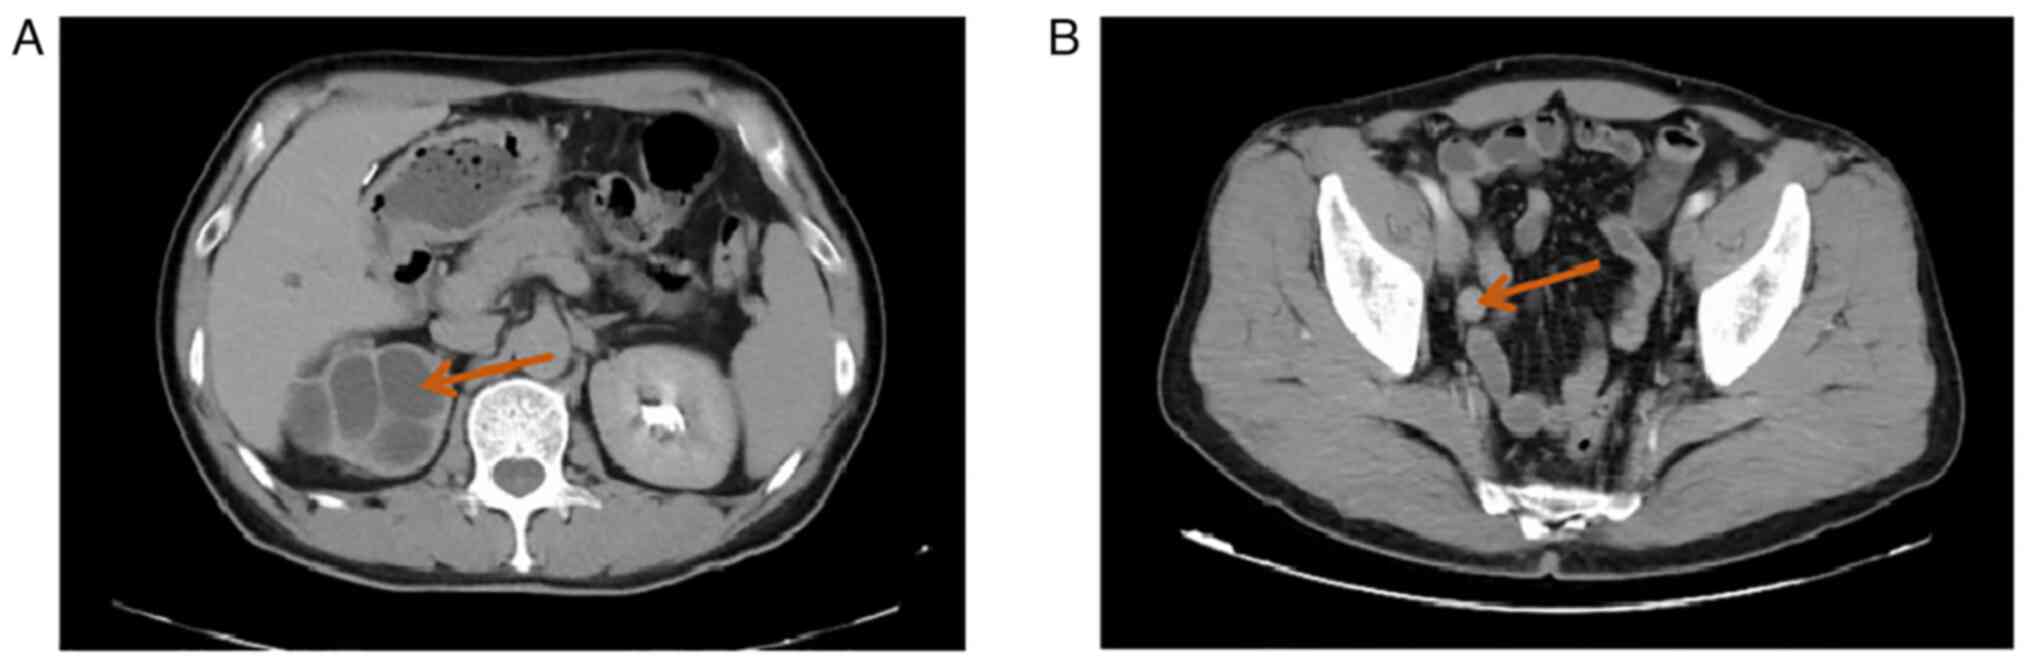

A 59-year-old male patient was admitted to the Department of Urology of the Affiliated Hospital of Zunyi Medical University (Guizhou, China) in November 2021 with no apparent cause of terminal carnal hematuria for >3 months. The patient had no urinary frequency, urgency, or painful urination and no significant lumbar pain. He had undergone laparoscopic cholecystectomy 20 years ago and denied family history of hereditary disease. Renal function tests showed blood creatinine 101 µmol/l, uric acid 402 µmol/l, GFR: right kidney, non-functional; and left kidney 62.03 ml/min. Computed tomography (CT) suggested fluid in the right kidney and upper right ureter, multiple cysts in the right kidney with partial marginal calcification (Fig. 1A), dilatation and fluid in the middle and lower right ureter, slight thickening of part of the ureteral wall, and occupying lesions observed in the ureter (Fig. 1B). Cystoscopy suggested that a persistent hematuric ejection was observed at the opening of the right ureter. The initial diagnosis was: i) Right ureteral space-occupying lesion: tumour; ii) right hydronephrosis with no function and iii) right renal cyst. Preoperatively, the possibility of renal malignancy was not considered. After perfect preoperative preparation, laparoscopic right nephrectomy and right ureteral resection was performed under general anesthesia, and the resected tissue was sent for pathological examination.

Figure 1

Computed tomography of the whole abdomen. (A) Hydronephrosis of the right kidney with multiple cysts in the right kidney and partial marginal calcification. (B) Occupational lesion in the right lower and middle ureter.